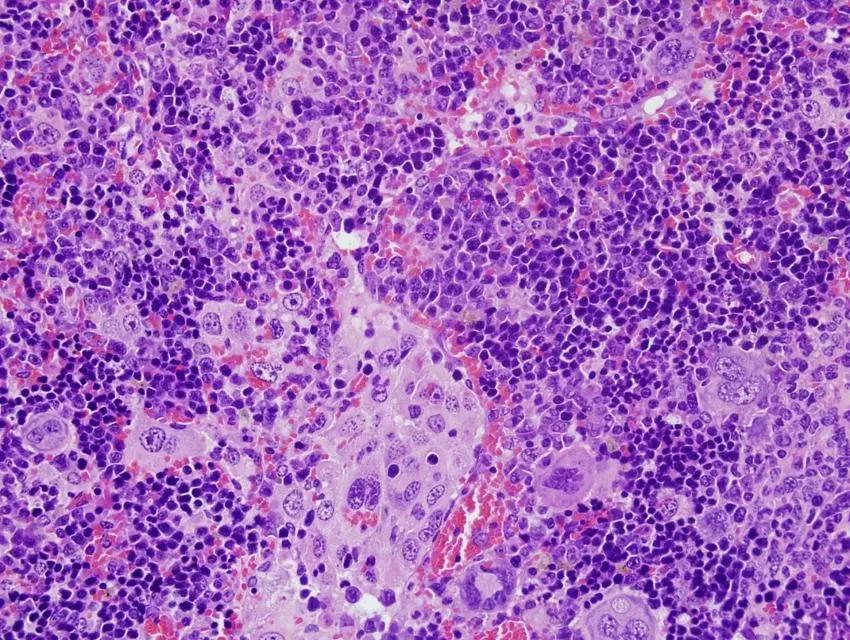

Un equipo liderado por investigadores del Centro de Investigación del Cáncer, centro mixto del Consejo Superior de Investigaciones Científicas y la Universidad de Salamanca (CIC-CSIC-USAL), ha realizado un catálogo completo de las mutaciones de un gen presentes en el linfoma periférico de células T, un tipo de tumor de los glóbulos blancos de la sangre.

El estudio, publicado en la revista 'EMBO Journal', identifica los diferentes tipos de mutaciones que provocan la activación descontrolada de este gen, denominado VAV1. Su identificación puede contribuir al desarrollo de fármacos específicos personalizados para frenar la progresión de esta patología, que se caracteriza por su agresividad, la falta de tratamientos efectivos y la alta mortalidad.

Los linfomas periféricos de células T se desarrollan a partir de los linfocitos T, unas células del sistema inmune cuya función es reconocer y destruir aquellas células que se han convertido en peligrosas, bien por haberse transformado en células cancerosas o por haber sido infectadas por virus como, por ejemplo, el SARS-CoV-2. Estas funciones positivas, sin embargo, se vuelven dañinas cuando los linfocitos T sufren alteraciones genéticas que los hacen proliferar de forma descontrolada y promover la formación de linfomas.

En este trabajo los investigadores demuestran que el 51% de mutaciones que afectan al gen VAV1 promueven su activación descontrolada y que, además, dichas alteraciones no son todas iguales. "Existen cinco tipos diferentes y, según la mutación que se presente, se desarrollan distintas características clínicas tanto desde el punto de vista de su malignidad como de las opciones terapéuticas", explica Javier Robles Valero, autor del estudio junto con Xosé R. Bustelo, ambos investigadores del CIC.

El estudio también ha desarrollado un modelo animal que permite generar linfomas en ratones tras la expresión de mutantes de VAV1 en linfocitos T sanos. "Usando técnicas genómicas y bioinformáticas hemos podido comprobar que estos linfomas reproducen la gran mayoría de las características clínicas, patológicas y moleculares de los linfomas periféricos de células T en los pacientes", añade el investigador del CSIC.